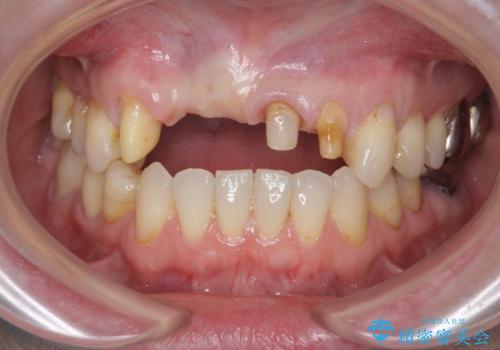

前歯が折れた 前歯部審美セラミックブリッジ治療

- ブリッジの根元が折れ、審美性の改善・治療を求めて来院されました。

保存の難しい歯を抜去しロングブリッジによる補綴を選択しました。

- 57万円(仮歯・ファイバーコア・ジルコニアクラウン×5)費用は治療当時の料金となります